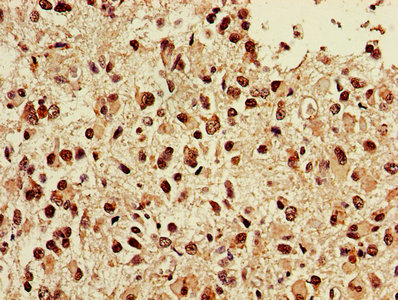

IHC image of CSB-PA10479A0Rb diluted at 1:400 and staining in paraffin-embedded human glioma performed on a Leica BondTM system. After dewaxing and hydration, antigen retrieval was mediated by high pressure in a citrate buffer (pH 6.0). Section was blocked with 10% normal goat serum 30min at RT. Then primary antibody (1% BSA) was incubated at 4°C overnight. The primary is detected by a biotinylated secondary antibody and visualized using an HRP conjugated SP system.